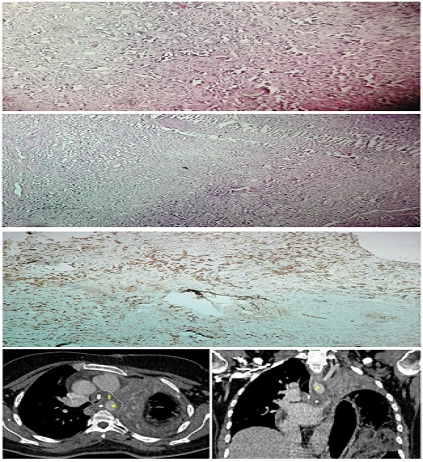

Pazopanib in Pulmonary Epithelioid Hemangioendothelioma: Report of a Case

Ibtihal Ahalli, Karima Oualla, Loubna Hejjane, Raihana Boujarnija, Kaouthar Messoudi, Adil Mai, Fatima Zahrae Er Reggad, Lamiaa Amaadour, Zineb Benbrahim, Samia Arifi, Badr Alami, Laila Chbani, Nawfel Mellas

International Journal of Innovative Research in Medical Science·February 21, 2020